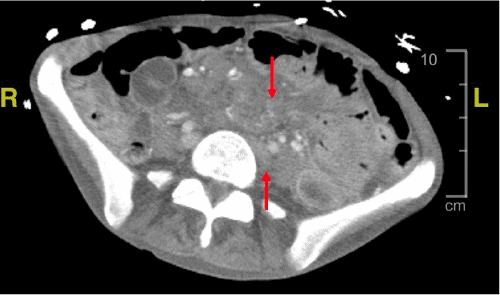

A CT scan of the abdomen (Figure 1) demonstrated marked hepatosplenomegaly (spleen measuring 23 × 15 × 9 cm) and retroperitoneal and mesenteric lymphadenopathy. The differential diagnosis included metastatic lymphoma, disseminated Mycobacterium avium-intracellulare complex (MAC), Castleman disease, and tuberculosis. The patient was started on PCP prophylaxis (atovaquone) and broad-spectrum antibiotics (vancomycin and cefepime). Cardiology was consulted, and a transthoracic echocardiogram showed no acute abnormalities. A multidisciplinary team (hematology/oncology, infectious disease, internal medicine, and general surgery) recommended splenectomy for both diagnostic and therapeutic purposes.

Figure 1. Abdominal and Pelvic CT Imaging with IV Contrast. Published with Permission

(C) Axial view of the pelvis demonstrating mesenteric and retroperitoneal lymphadenopathy